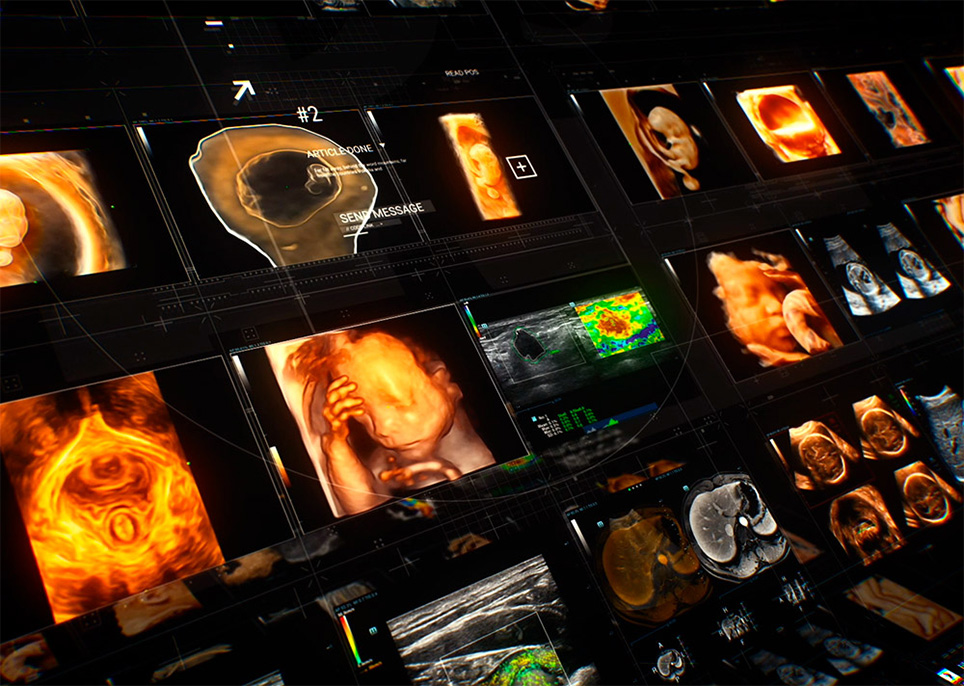

Met de ontwikkeling van de samenleving en de toenemende bezorgdheid over de gezondheidsproblemen van vrouwen, zijn steeds meer vrouwen zich bewust van het belang van regelmatige gynaecologie-onderzoeken met behulp van echografie. De groeiende vraag naar echografisch onderzoek heeft ongetwijfeld geleid tot een nieuwe uitdaging voor echografisten, om nog maar te zwijgen van het feit dat de vraag steeds meer gesegmenteerd is. Om het proces te vereenvoudigen en meer vrouwen te voorzien van hoogwaardige diagnostische echografiediensten, zet Mindray zich in voor innovatie en biedt een volledig pakket slimme oplossingen voor de gezondheidszorg voor vrouwen en kinderen, mogelijk gemaakt door zone intelligence?. Wij hopen de echografisten een 'magisch wapen' in handen te geven waarmee ze meerdere onderzoeksscenario's aankunnen, van pre-zwangerschap en zwangerschap, tot postpartumherstel en pasgeborenen, waardoor hun gezondheid verder wordt beschermd.

Volledige reeks slimme oplossingen voor de gezondheidszorg voor vrouwen en kinderen, mogelijk gemaakt door Zone Intelligence?